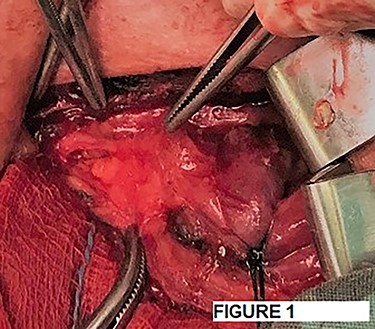

After a careful preparation of the anatomical structures of the neck and exposure of the thyroid gland, we proceeded to recognition of the parathyroid gland (Fig. 1). Then, glycerol solution was injected with a syringe of 2.5 ml and a needle of 26 gauges, to the loose connective tissue between the thyroid gland capsule and the parathyroid gland (Fig. 2). The amount that was administered was such as to produce the desired effect of tissue separation. By injecting the glycerol solution, the tissues swell, the size of the surgical field increases and the anatomical preparation of the parathyroid gland becomes simpler and with minimal parathyroid gland handling. A field like a glass is created, where the vasculature and the limits of the parathyroid gland are distinguished (Fig. 3). After that, a carefully dissection with a Mayo dissection scissor leaves the parathyroid gland intact. This technique is called TDSI.